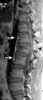

Congenital thoracolumbar vertebral wedging

Congenital vertebral anomalies are a collection of malformations of the spine. Most, around 85%, are not clinically significant, but they can cause compression of the spinal cord by deforming the vertebral canal or causing instability. [Source: Wikipedia ]